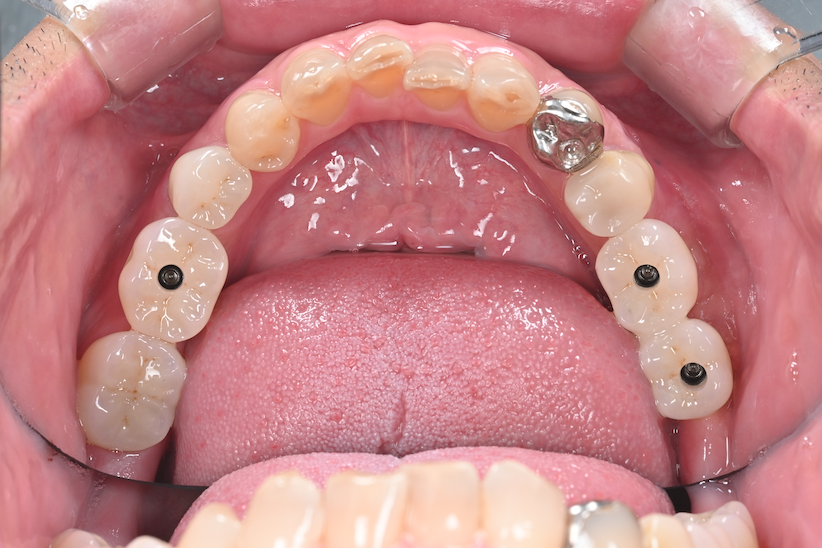

前歯部・臼歯部の

インプラント治療

タップで写真の拡大ができます。

主訴

噛めない

治療内容

上下インプラント埋入、サイナスリフト、GBR、ソケットシールド

治療期間

約1年

治療費用

5,000,000

治療の

リスク

創部の裂開、感染が起こった場合は骨造成のやり直しが必要になる可能性があります。上顎洞粘膜への穿孔が起こった場合、上顎洞炎を併発する可能性があります。